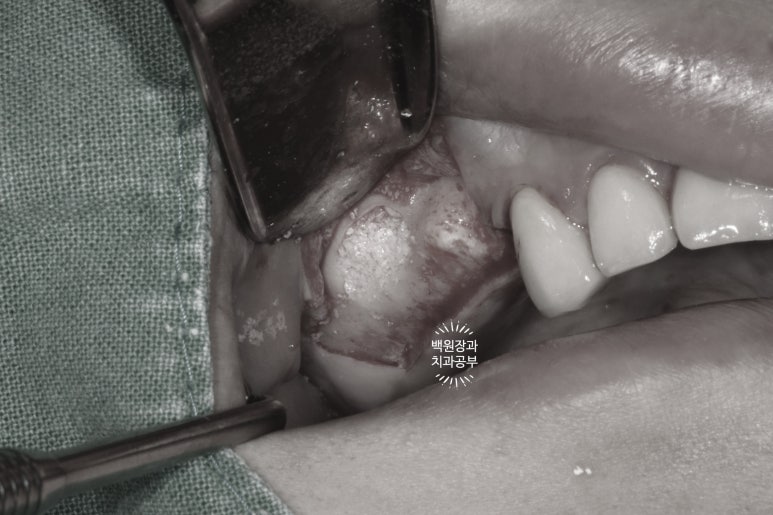

아까 보시던 얇은 상악동막을 기존의 치조골에서 박리 후, 원하는 만큼 뼈이식을 해둡니다.

저희 연세더좋은플란트치과는 주로 덴티움 (제노스) 사의 osteon III 합성골을 많이 사용합니다.

합성골은 제조 과정부터 아주 깔끔하며 (사체나 동물에서 뼈를 채득하는 것 보단... 물론 멸균은 하지만) 분해되면서 방출되는 칼슘 이온이 뼈를 만들어내는 세포를 보다 더 활성화 시킨다고 되어있습니다.

물론 여러 논문에서 상악동 뼈이식술을 위해 어떤 뼈이식재든 큰 차이는 없다고 되어있지만... 기왕 사용하는 것 국내 1위 합성뼈 제조 회사의 제품을 사용하는 것이 좋겠죠? ㅎㅎㅎ

혹시나 제 글을 보고 있는 치과의사 분들이 있다면... 가능하면 무조건 이 차폐막을 사용해드립시다.

저는 덴티움 사의 콜라겐 멤브레인을 사용하고 있습니다만... 어떤 회사의 제품이든 차폐막이 있고 없고의 차이가 큽니다. 수술 원가를 줄이기 위해 차폐막을 사용하지 않는 것은.... 자칫하면 고생해서 한 뼈이식이 의미가 없어지는 결과를 낳을 수도 있기에.. 정말 그러지 맙시다요.

수술결과를 보면, 기존 뼈이식이 되어있는 좌측에 비해 다소 적은 뼈이식이 된 것처럼 보입니다만,

상악동 뼈이식술은 항상 딱 필요한만큼만 뼈이식하는 것이 중요합니다.

너무 많은 뼈이식재를 넣으면... 결국 그 뼈이식재가 단단한 뼈가 되지 못하고 몸속에 담겨있기만 하기 때문이죠.

뼈이식재는 항상 과유불급입니다.